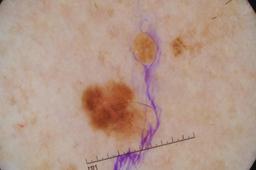

Evaluation set from the ML challenge: SIIM-ISIC Melanoma Classification.